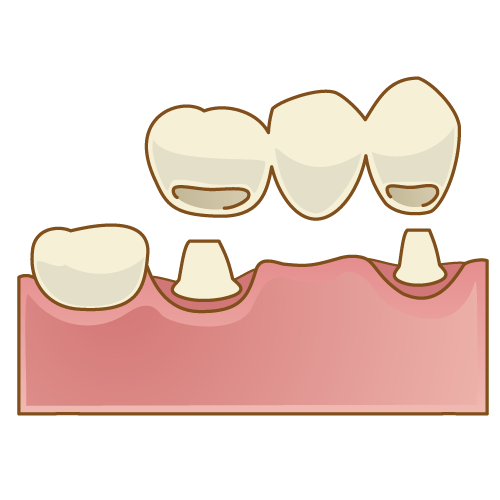

4-1:ブリッジ

ブリッジとは、失った歯の両隣にある健康な歯を土台にして、連結した固定式の人工歯を取り付ける治療法です。

1本または数本の歯を失い、その両隣の歯が健康な場合に適した治療になります。

- 固定性

→ブリッジは両隣の歯を支えにして固定されるため、安定感があります。 - 自然な見た目

→自分の歯に近い見た目を再現でき、違和感が少ないです。 - 治療期間が短い

→一般的に、2〜3回ほどの通院で治療が完了します。 - 治療費が安い

→保険適用(3割負担)の場合、欠損歯1本あたり1.5万円~3万円ほどで装着できます。

- 健康な歯の削除

→両隣の健康な歯を削る必要があり、その歯に負担がかかります。 - 耐久性の問題

→保険適用で作成されたブリッジの寿命は約7年~8年ほどで、かけたり割れたりすると再治療が必要になることがあります。

ブリッジについて、もっと詳しく知りたい方は以下記事をあわせてご覧くださいね!